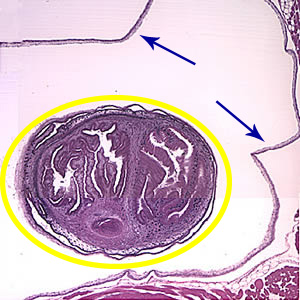

A 49-year-old male immigrant from Mexico was seen at a local medical facility specializing in neural disorders for frequent headaches and occasional seizures. Figures A and B show what was observed on a hematoxylin and eosin (H & E) stained section of lesions detected in the right frontal lobe of his brain. Figure A was taken at 40× magnification and Figure B was taken at 100× magnification. What is your diagnosis? Based on what criteria?

Figure A